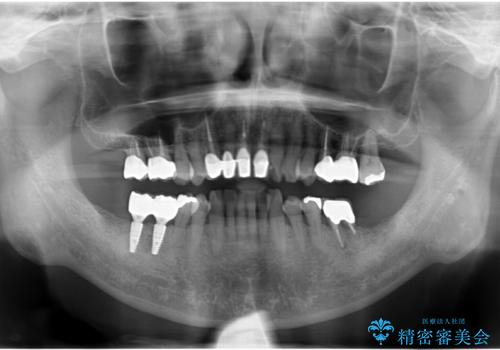

- 右下の奥歯が割れてしまい、抜歯を行いました。

ブリッジにできない位置であったため、インプラントでかめるようにしました。

また、向かい合う上の歯が挺出(伸び出してしまうこと)しており、インプラントを入れることが難しかったため、長さを短くかぶせ治しました。

また、上顎前歯以外の根の治療のやり直しを行いました。

- 約250万円 右下67 インプラント2本(ストローマンインプラント20万円、カスタムアバットメント10万円、シリンダーTeC 2万円 以上2本、マイナーGBR5万円) 再根管治療 (前歯 9万円x1、小臼歯11万円x1 大臼歯:専門医による再治療 15万円x3本) ジルコニアクラウン(右上2367、右下I6I7、左上56 10万円x8 )仮歯 1万円x8本 ファイバーコア 2万円x5 セラミックインレー(左上5) 7万円x1 フラットタイプナイトガード 3万円費用は治療当時の料金となります